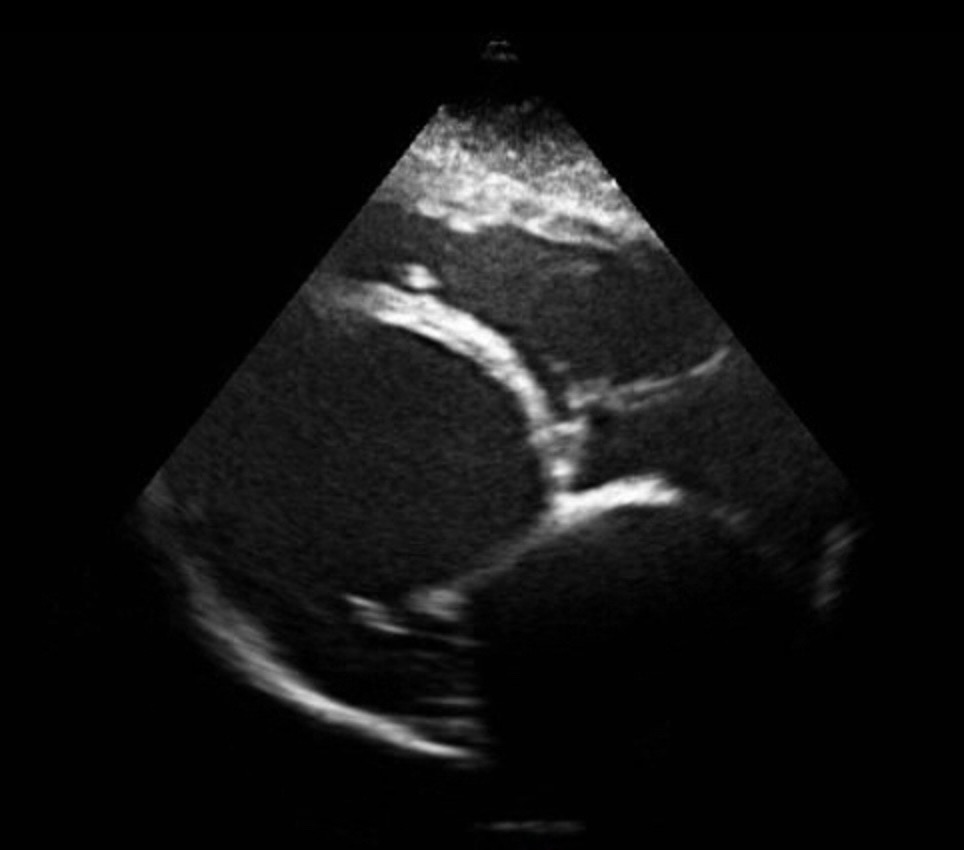

Eje corto y eje largo ecocardoscopia con dilatación severa ventrículo izquierdo, anillo mitral y aurícula izquierda, acinesia global ventrículo izquierdo, ausencia derrame pericárdico.